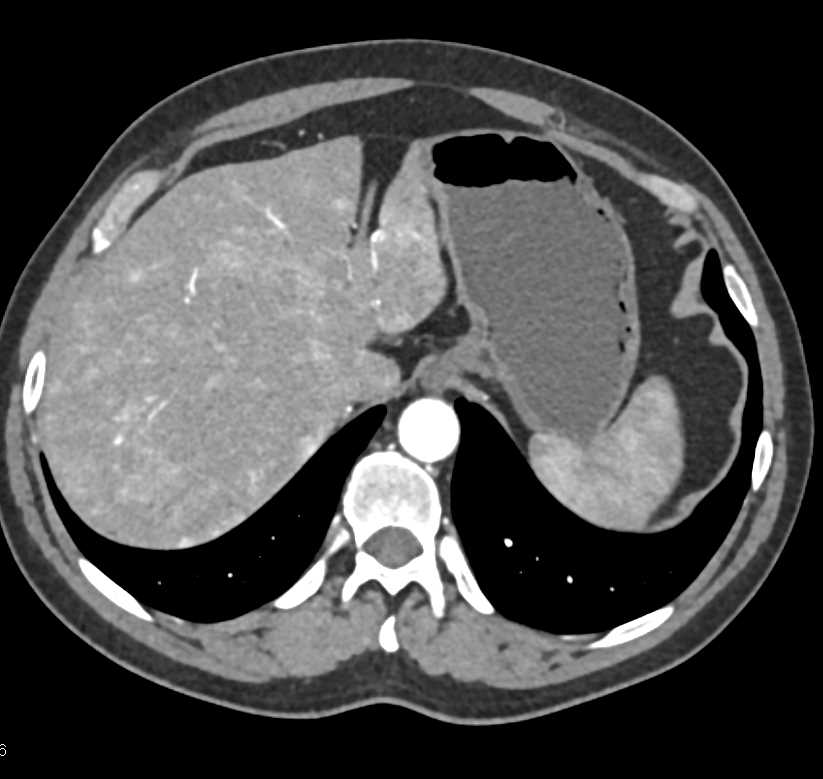

Giant Cavernous Hemangioma of the Liver